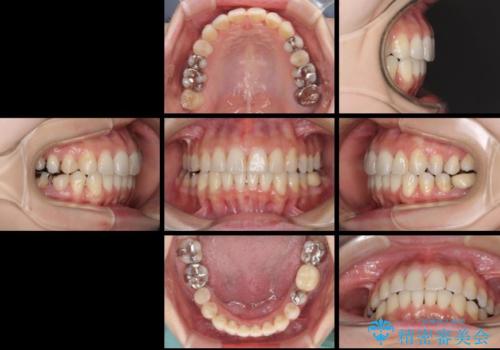

上顎骨拡大を併用したインビザライン矯正

- 上下のデコボコと奥歯の咬みにくさを気にして来院された患者様です。

上顎骨の幅が下顎骨よりも小さいので、拡大装置により骨幅を広げて上下関係を改善し、その後インビザラインにて歯並びを整えることとしました。

上下の骨幅を改善したことで、スムーズに歯列矯正を行うことができました。

矯正治療中に近医で銀歯を外す治療を開始したため、治療後に奥歯の咬み合わせが不十分ですが(こちらは近医での治療により改善するとのこと)、歯列と咬み合わせが改善され、患者様には大変満足していただきました。